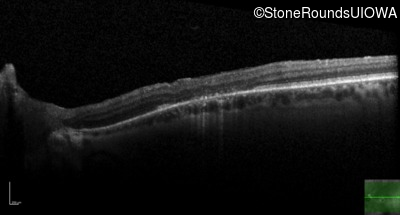

Optical Coherence Tomography - Right - 20/32 +1

Exemplar / OCT Stack

OCT Stack